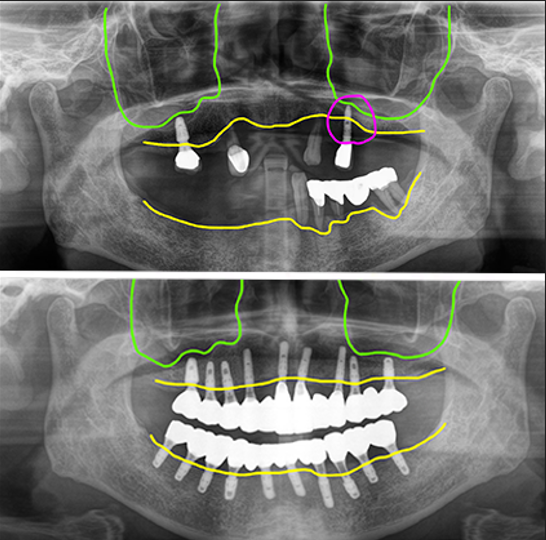

오늘 설명해 드릴 사례는 60대 여성 환자로 예전에 식립한 임플란트 중 한 개가 임플란트주위염이 생겨 뼈가 거의 다 녹았고, 나머지 남아있는 치아들도 모두 흔들거려 전체임플란트로 치료하기로 했어요.

여러 개의 치아들이 이미 상실되어 있었고, 남은 치아들은 치아뿌리의 염증이 있거나 치주염으로 이미 많이 흔들리는 상태였습니다.

그리고 예전에 식립해 둔 임플란트 중 한 개가 임플란트 주위염으로 상태가 좋지 않았습니다.

그러나 전반적인 가용골은 충분하신 상태여서 복잡한 뼈이식없이 전체임플란트 진행이 가능할 것으로 보였습니다.

상악에 임플란트주위염이 있는 임플란트와 남은 자연치들을 모두 제거한 후 10개의 임플란트를 식립했고, 아래 전체적으로 흔들리는 보철과 치아들을 제거한 후 임플란트 10개를 식립했습니다.

식립한 임플란트 모두 초기고정이 좋아 바로 지대주를 연결해서 스캔한 후 디자인해서 PMMA로 밀링해서 수술당일 임시치아를 완성해서 세팅해 드렸어요.

대체로 양호한 뼈상태 로 무난하게 최종보철 완성

수술후 4개월 차에 최종보철을 만들기 위한 스캔을 했고 맞춤지대주에 지르코니아 브릿지타입의 보철을 만들어서 완성했어요.

보철은 가능한 너무 뚱뚱하지 않게 만들어서 위생관리에 도움이 되도록 했고, 치간치솔을 사용할 수 있도록 만들었습니다.

전체 내원 4회 (수술, 실밥, 스캔, 세팅) 치료기간 4개월에 모든 치료를 완료하셨습니다. 심근경색 병력이 있었지만 관리가 잘 되고 있었어요.

수술시 아스피린 복용 중단하고 수술 잘 진행되었으며 환자의 협조도 좋아서 모든 임플란트가 다 성공적으로 골융합이 되었습니다. 4년전에 수술하시고 현재까지 정기검진 잘 오고 관리가 잘 되고 있습니다.